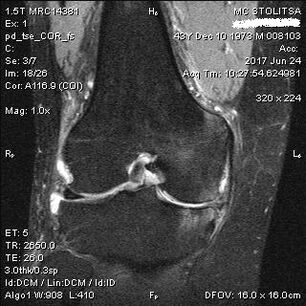

Diagnosis arthrosis tina gabungan dengkul lumangsung di kantor rheumatis atanapi orthopedist. Dokter nguji hiji gabungan anu kapangaruhan, palpates, palaku pikeun keluhan sareng naroskeun patarosan tambahan. Ngalaksanakeun sababaraha tes - contona, naroskeun sabar pikeun ngabengkokkeun sukuna atanapi leumpang sababaraha léngkah. Teras, upami éta dipikabutuh pikeun netelakeun tahap panyerahan atanapi alam parobahan patologis, anjeunna bakal ngarujuk anjeun pikeun studi tambahan. Salaku conto, pikeun ngitung Tomografi atanapi Radiografi.